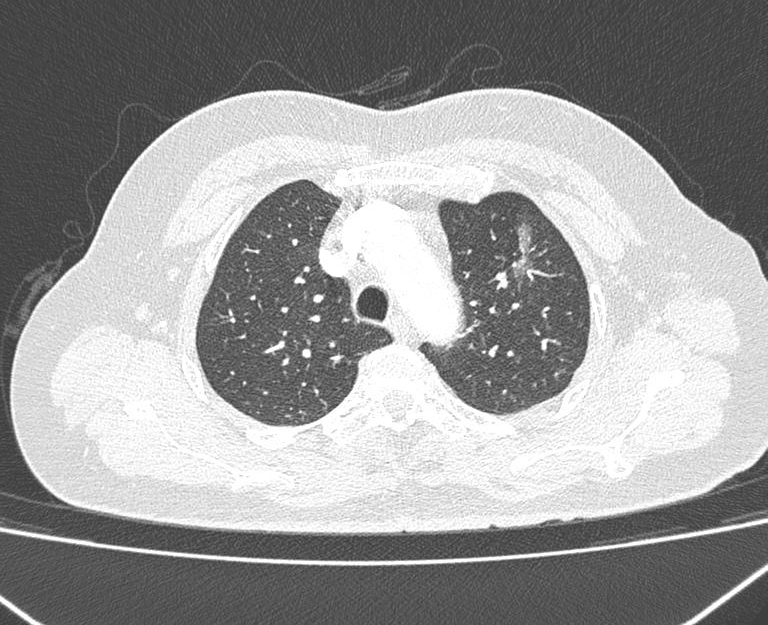

时间回到 2022 年,当 58 岁的张阿姨在常规体检中,意外发现左上肺存在一枚肺结节。忧心忡忡的她立刻前往外院就诊,胸外科医生通过读片判断,这枚结节大概率是早期肺癌,建议她立即接受手术治疗。突如其来的 「坏消息」 让张阿姨慌了神,「当时一听说可能是癌症,我脑子都乱了,总觉得手术是大事,想多找专家问问情况。」张阿姨了解到黄山华泽医院常务副院长、呼吸与危重症医学科主任医师陈新民在肺结节诊疗方面有丰富经验,便带着所有检查资料前往咨询。陈新民副院长仔细询问病史、反复研读胸部 CT 影像后,结合临床经验给出专业判断:这枚结节属于纯磨玻璃结节,边界清晰,虽直径已超 2 cm,但首次发现且无明显恶性特征,即便为恶性,短期内也不会快速进展。「考虑到您年龄不算大,既要保障生命周期,也要不影响正常工作生活,目前更适合 3-6 个月定期复查,动态观察结节变化。」陈院长的耐心解释,让焦虑的张阿姨渐渐安下心来。

此后三年,张阿姨严格遵循陈院长的诊疗建议,定期复查。每一次 CT 检查后,陈院长都会细致对比结节的大小、密度、形态,为她建立专属的诊疗档案。

转折发生在 2025 年 6 月份的随访中。陈院长在对比最新 CT 影像时发现,张阿姨的肺结节出现了明显变化:直径增大、密度增高,不仅出现近 20% 的实性成分,还伴随分叶、毛刺、血管集束征、空泡等典型恶性肿瘤特征。同时,医院肺结节 AI 诊断系统也提示 「恶性可能性大」。「结节已经到了需要干预的时机,不过您别担心,我们会尽快组织多学科专家会诊,制定最适合您的方案。」 陈院长第一时间将情况告知张阿姨,并立即启动医院肺结节诊治中心的多学科协作(MDT)机制。

2025 年 6 月